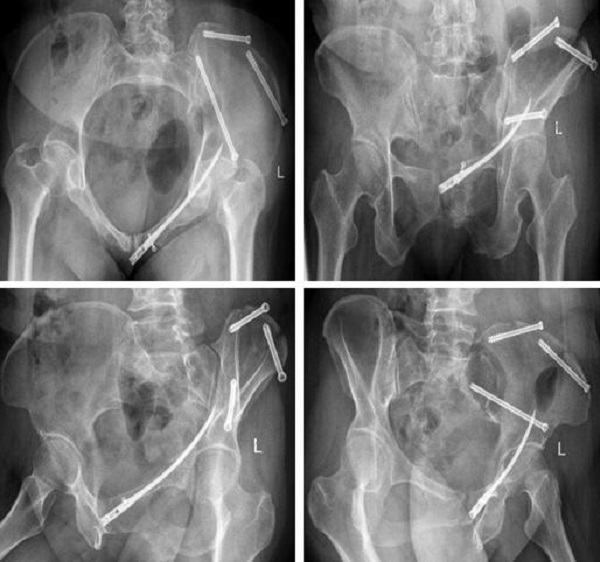

术前,创伤骨科郭永良主任医师团队应用MIMICS软件重建患者骨盆LC—II通道螺钉方向和长度,术中郭永良主任亲自主刀,使用Schanz针协助闭合复位,结合术前模拟通道螺钉方向精确制导,以最小的创伤将LC-Ⅱ通道螺钉顺利置入合适位置,而且完美避开神经及血管损伤,仅通过3枚螺钉使骨盆LC—II型骨折得到有效的稳定固定。

术后复查: